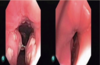

Qual o nível e a configuração da obstrução segundo o VOTE e NOHL?

Fechamento anteroposterior em velofaringe (V pela VOTE) ou orofaringe (O, pela NOHL).